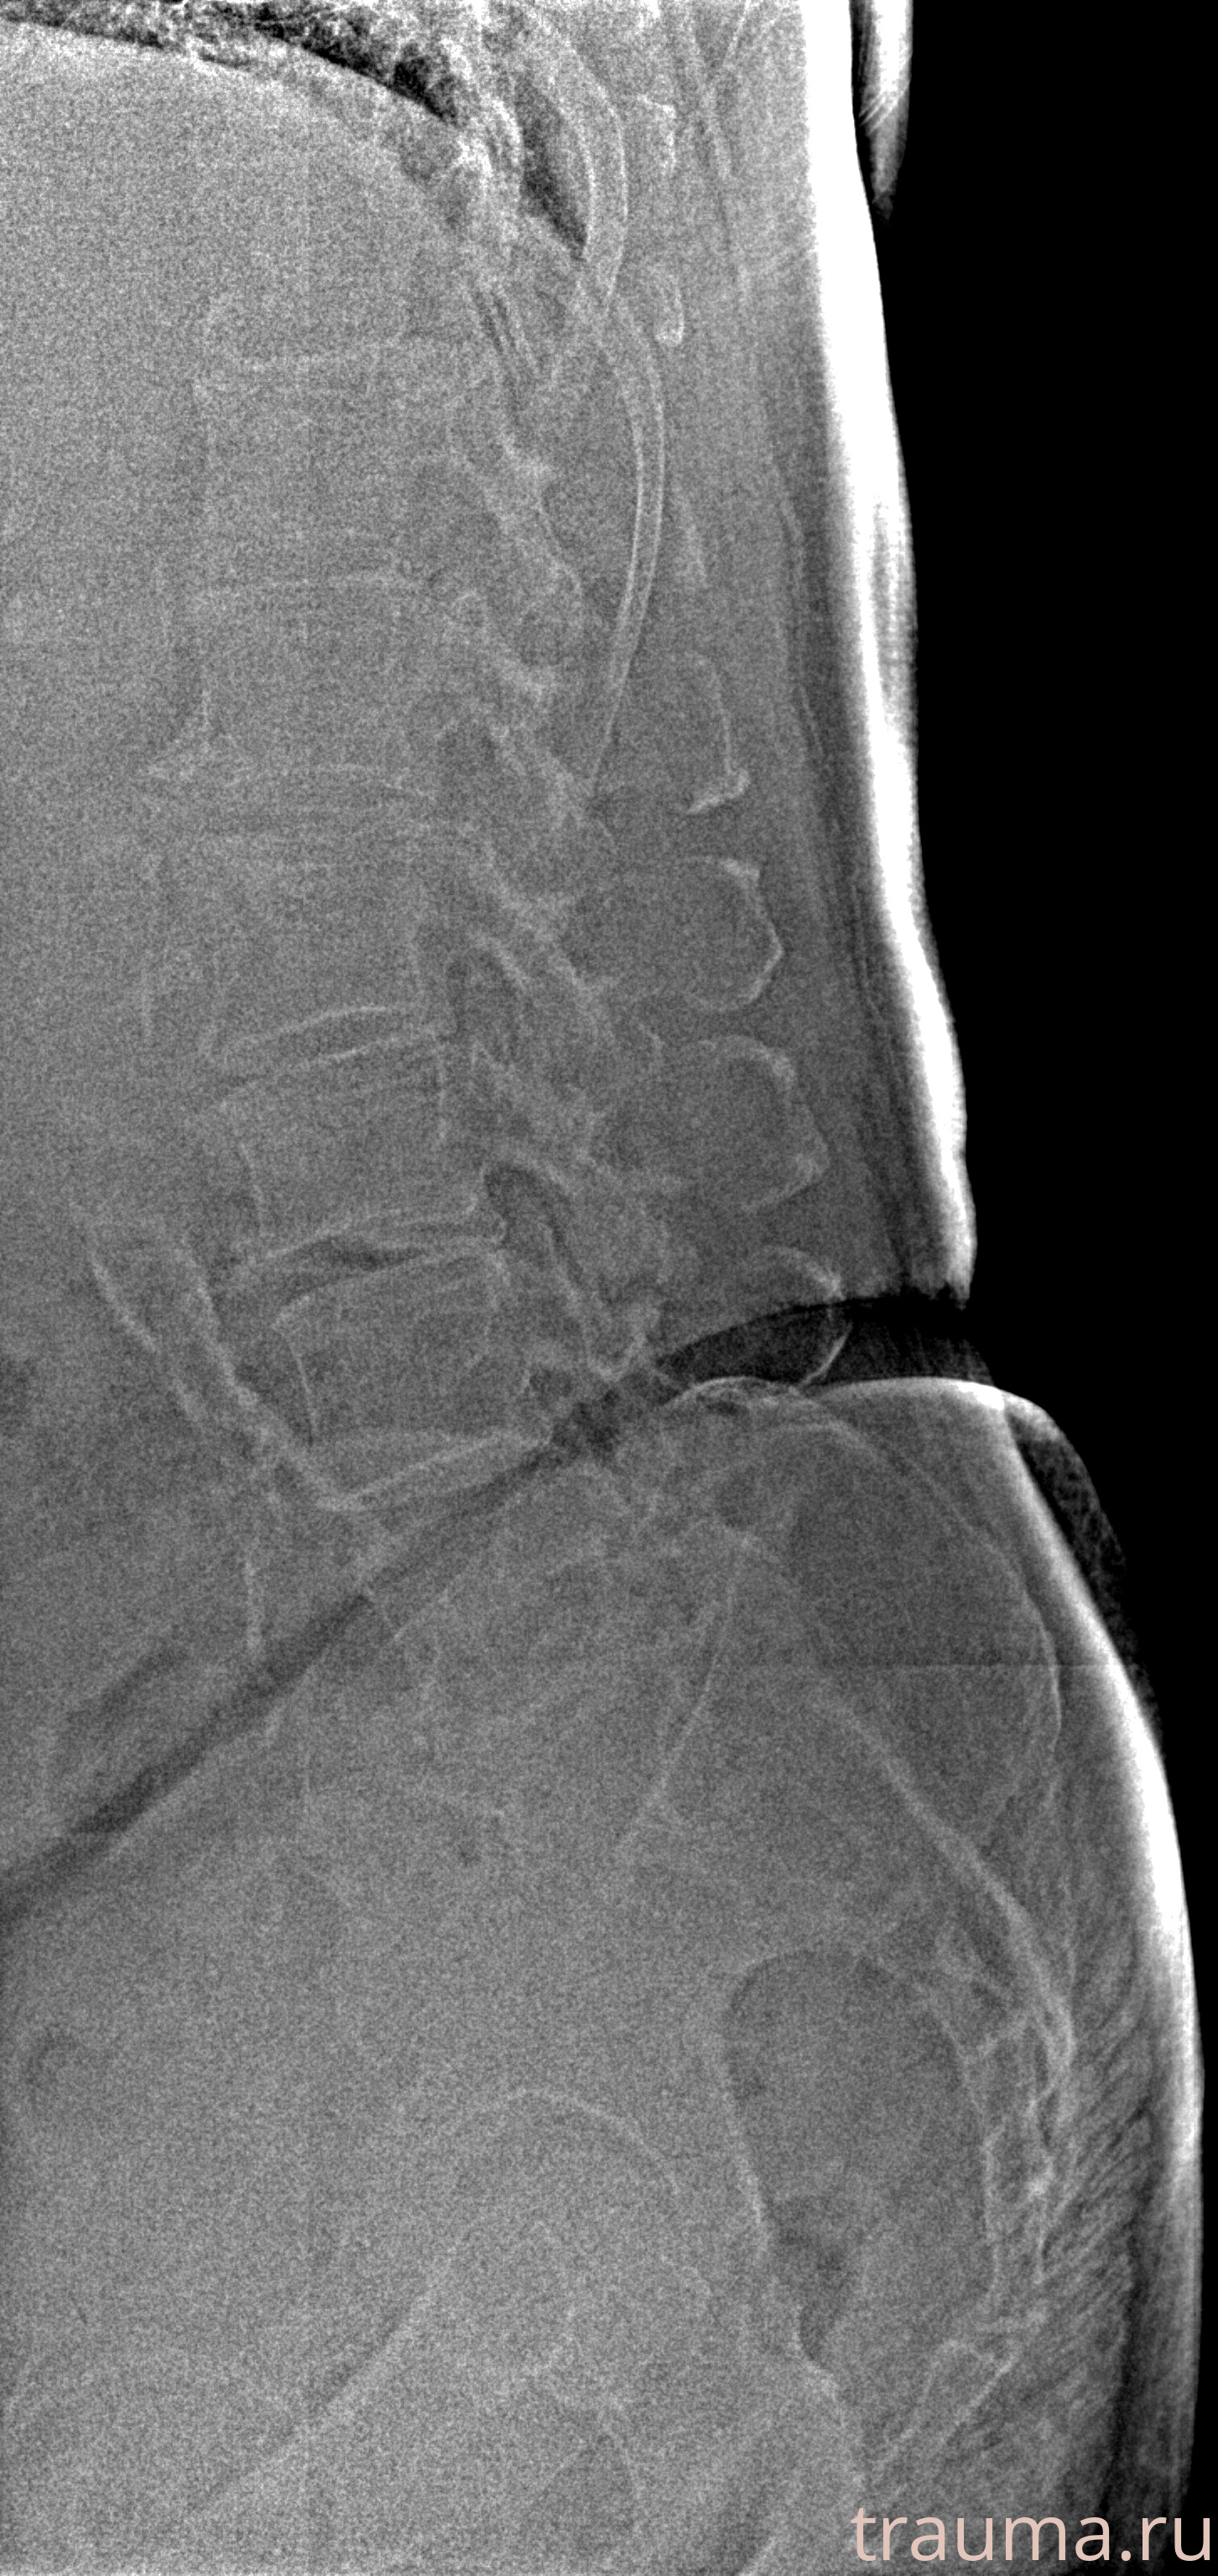

Рентгенограммы

Рентген на дому: по вашему адресу приезжает врач-рентгенолог, травматолог-ортопед с мобильным рентгеновским аппаратом, проводит диагностику травмы или заболевания, делает необходимые рентгенограммы, дает рекомендации по дальнейшему лечению. Получить качественные снимки в домашних условиях возможно благодаря уникальной методике, разработанной МосРентген Центром для института  Склифосовского